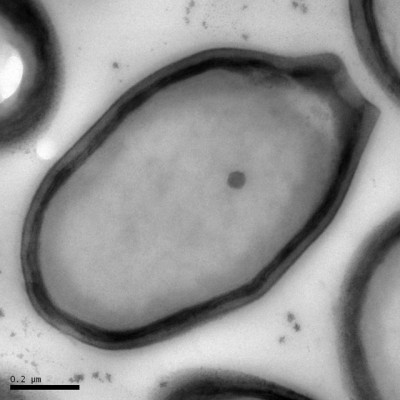

ไวรัสแพนโดรา

นักวิจัยขุดพบไวรัสขนาดใหญ่ที่สุดอีกครั้ง คราวนี้ใหญ่กว่าไวรัสที่เคยพบเป็น 2 เท่า และคาบเกี่ยวระหว่างนิยามของ "สิ่งมีชีวิต" กับ "ไวรัส"

ตามปกติไวรัสทั่วไปมีขนาดใหญ่แค่ 20-300 นาโนเมตร และไวรัสส่วนมากอย่างเช่น ไวรัสไข้หวัดใหญ่และไวรัสเอชไอวี (HIV) นั้นมียีนแค่ 10 ยีนหรือน้อยกว่านั้น ทว่าไวรัสที่เพิ่งค้นใหม่นี้มียีนกว่า 2,500 ยีน

ไลฟ์ไซน์ระบุก่อนหน้านี้ราว 10 ปีที่ผ่านมา มีขนาดใหญ่กว่า 700 นาโนเมตร และมียีนมากกว่า 1,000 ยีน ซึ่งเป็นลักษณะทั่วไปของแบคทีเรีย ทำให้ไวรัสดังกล่าวได้ชื่อว่า "มิมิไวรัส" (mimivirus) ซึ่งหมายถึงการเลียนแบบจุลินทรีย์

ส่วนไวรัสขนาดใหญ่ที่สุดที่เพิ่งค้นพบนี้ มียีนราวๆ 2,500 ยีน มีขนาดเล็กกว่าเส้นผม 100 เท่า และมองเห็นผ่านกล้องจุลทรรศน์แบบใช้แสง ซึ่งต่างจากไวรัสทั่วไป

รูปทรงของไวรัสคล้ายคลึงเหยือกของกรีกโบราณ จึงเป็นที่มาของชื่อว่า "แพนโดราไวรัส" (pandoraviruses) ซึ่งทีมวิจัยพบระหว่างการเตรียมค้นหาไวรัสใหม่ที่มียีนอยู่ในช่วง 1,000-2,000 ยีน

นักวิจัยพบไวรัส แพนโดราไวรัส ซาไลนัส (Pandoravirus salinus) ซึ่งถูกขุดพบจากปากแม่น้ำตันเควนทางชายฝั่งตอนกลางของชิลี ส่วนไวรัส แพนโดราไวรัส ดัลซิส (Pandoravirus dulcis) อีกชนิดขุดขึ้นจากใต้สระน้ำจืดในเมลเบิร์น ออสเตรเลีย

สิ่งคล้ายไวรัสแพนโดรานั้นถูกพบครั้งแรกเมื่อ 13 ปีก่อน แต่ไลฟ์ไซน์ระบุว่า ครั้งนั้นยังไม่ถูกระบุว่าเป็นไวรัส ส่วนไวรัสขนาดใหญ่ที่เพิ่งพบนี้ เดิมทีถูกเข้าใจผิดว่าเป็นแบคทีเรีย ซึ่งทีมวิจัยพบอยู่ในตัวอะมีบา

หลังอะมีบากลืนกินแพนโดราไวรัสเหล่านี้เข้าไป 2-4 ชั่วโมง นิวเคลียสของอะมีบาก็เปลี่ยนรูปไปอย่างไม่เหลือเค้าเดิม แล้วที่สุดก็หายเกลี้ยง เมื่ออะมีบาตายแล้วก็มีไวรัสแพนโดราอีกประมาณ 100 ไวรัสออกมา

มียีนของไวรัสแพนโดรากว่า 93% ที่เรายังไม่รู้จัก ซึ่งทำให้กำเนิดของไวรัสยังเป็นปริศนา และจากการวิเคราะห์จีโนมของพวกมันบงบอกว่า ไวรัสแพนโดรานั้นไม่ใกล้เคียงกับตระกูลไวรัสใดๆ ที่เรารู้จัก

อามีบาที่ถูกไวรัสแพนโดรายึดครอง